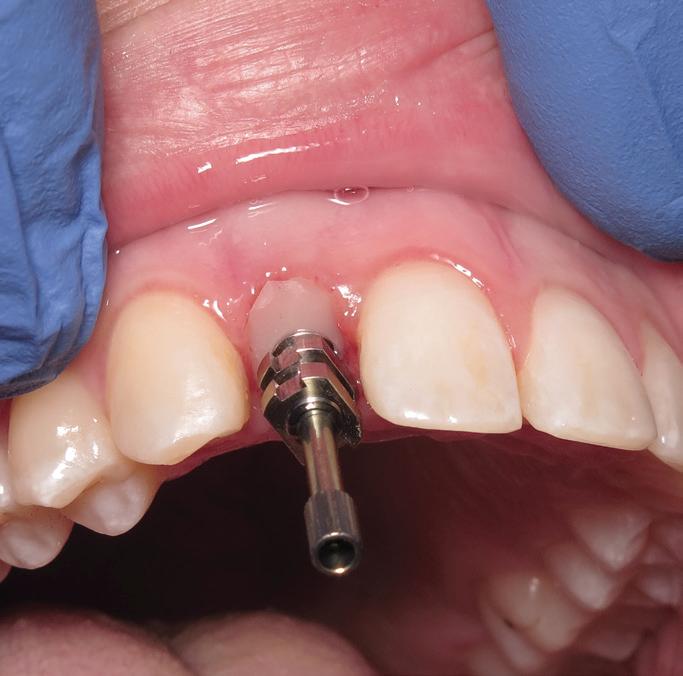

Tooth replacement from extraction to restoration. 3. Second-stage and impression procedures

The third part of this series reviews uncovering of implants that were buried in a 2-stage approach, provisionalization of the implant, and impression and scanning techniques.1 These techniques are all crucial for the final restorative outcome of the implant. The uncovering and second-stage procedures set the foundation for the shape and position of the soft tissue, which are very important esthetic factors. This information must also be properly transferred to the laboratory via a highly accurate impression so the laboratory has as much information as possible. If these steps are done properly, the result will be implant crowns that are easy to seat, biologically ideal, and esthetically pleasing.

Second-stage procedures